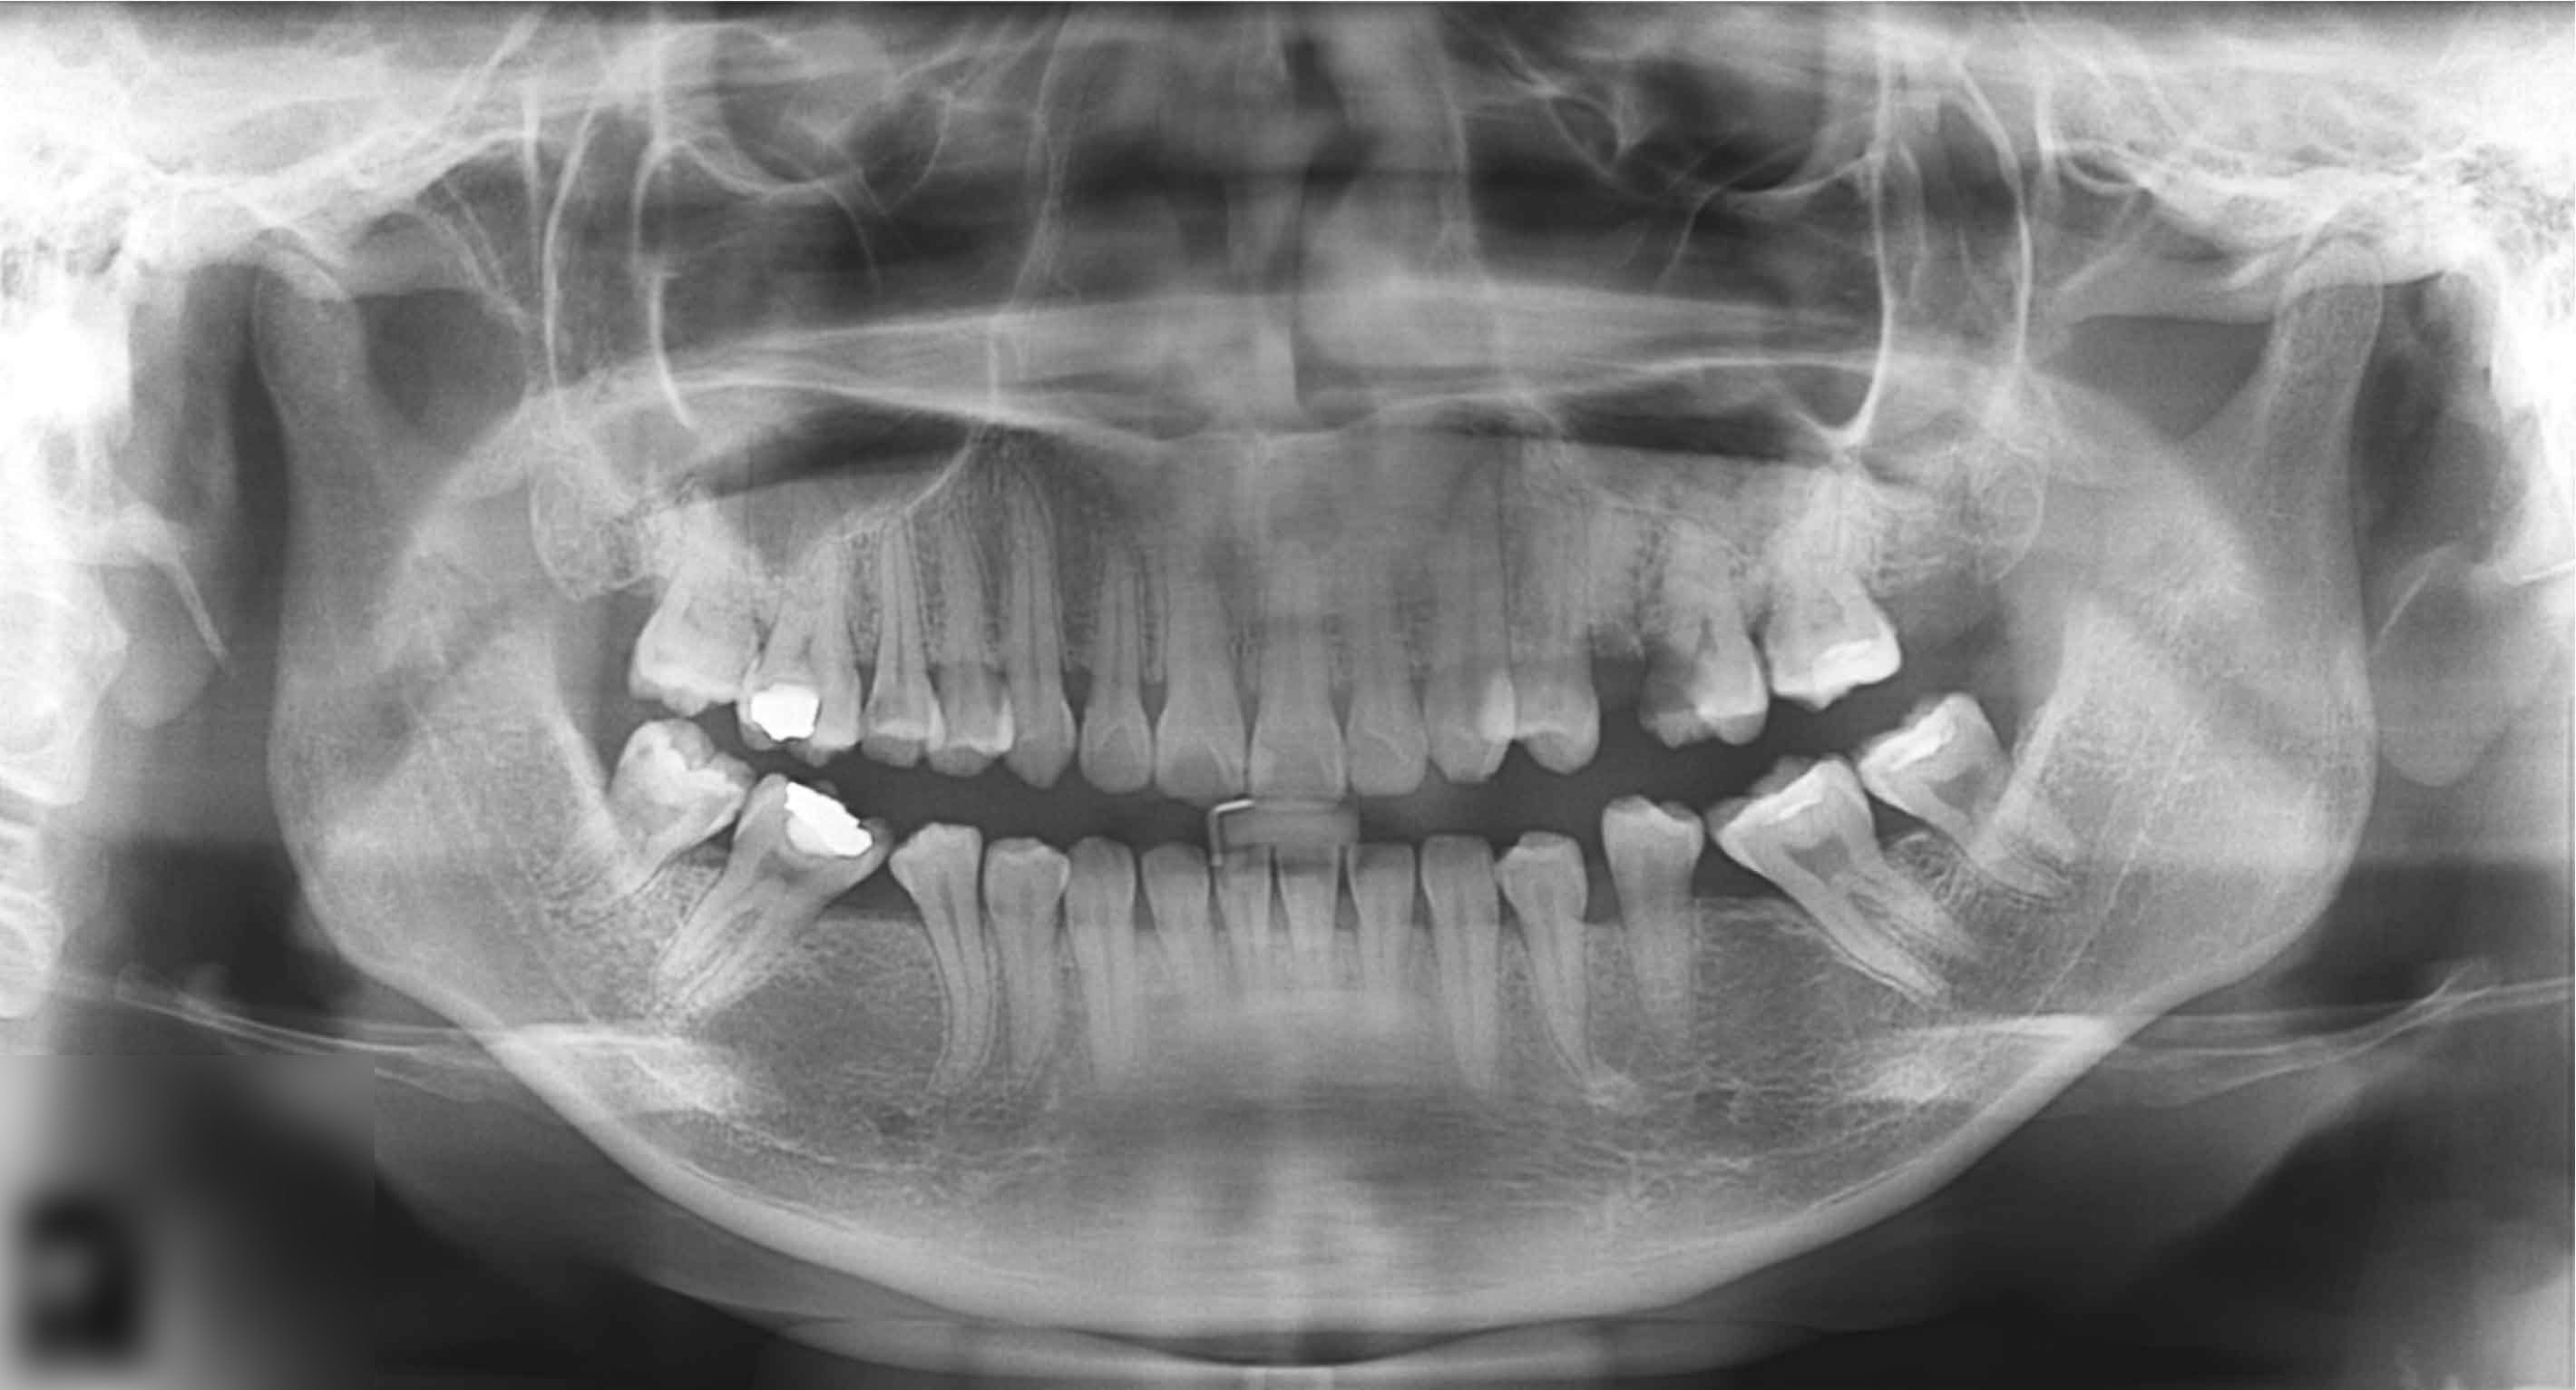

Pacientul Z.A. s-a prezentat la cabinet cu o durere insuportabilă localizată la nivelul maxilarului.

După prima ședință de tratament durerea a mai cedat. Pacientul colaorează mai bine și totodată manifestă interes pentru alternative ale plaului de tratament.

Planul de tratament recomandat a fost acceptat de pacient.

O nouă radiografie ne arată ameliorarea problemei inițiale. Tratamentele de canal au adus un aport substanțial la aceasta.